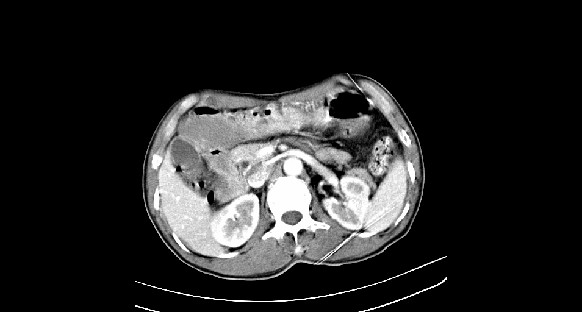

男性,70岁,体检b超发现左肾占位,请各位战友发表一下观点

左肾有两个病灶,且较大的病灶内可见点状钙化灶,增强扫描边缘也是呈渐进性强化,中央部分未见明显强化